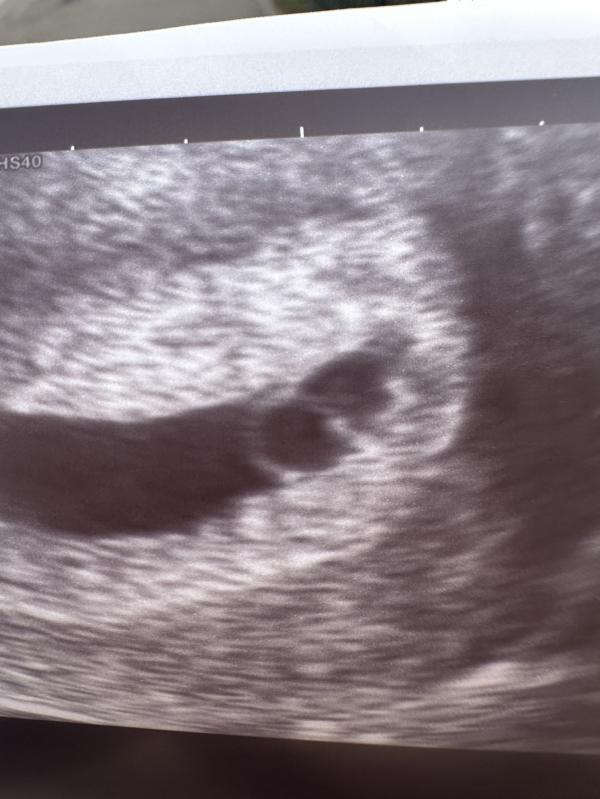

Переделала узи в другом месте, картина яснее не стала 😭

Остается ждать и молится 🥺

Через 3 дня схожу еще

Просто странно что яйцо не маленькое размером и у всех на этом размере был эмбрион , если все хорошо

Вы себя не накручиваете, просто рано пошли на узи . На 7 недели уже будет слышно сердцебиение малыша. Всё будет хорошо! 🤗